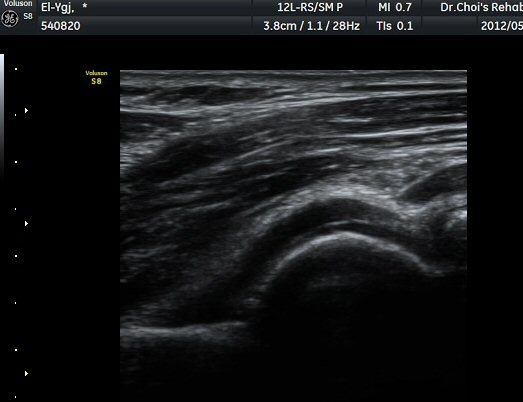

ÆÈ²ÞÄ¡ ³»Ãø Á¾´Ü¸é°ú Ⱦ´Ü¸é°Ë»ç¿¡¼­ ȰÂ÷ ¾Õ°ú °¥°í¸®µ¹±â¿Í(coronoid fossa)¿¡ ¼ö¾×Àú·ù°¡

°üÂûµÇ°í °¥°í¸®µ¹±â¿Í¿¡ °í¿¡ÄÚ »À µ¢¾î¸®°¡ °üÂûµÈ´Ù(±×¸² 2, 3).